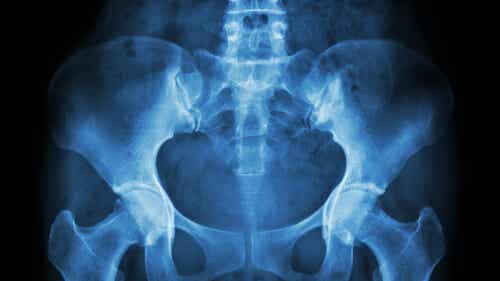

La necrosis avascular de la cabeza femoral es relativamente frecuente y suele afectar a pacientes de 20-50 años de edad. Las dislocaciones de cadera, las fracturas de cadera y otras lesiones de la cadera pueden dañar los vasos sanguíneos y afectar la circulación hacia la cabeza femoral. El proceso suele durar de meses a años. ¿Es suficiente la TAC para diagnosticar necrosis avascular de cadera? 3.Habitualmente la cirugía de prótesis total primaria de cadera está indicada a pacientes mayores de 60 años con artrosis, pero en la actualidad se presenta cada vez más en pacientes más jóvenes, donde se suman otras causas como la artritis reumatoidea, necrosis avascular, secuelas postraumáticas y pellizcamiento de cadera.La necrosis avascular es la muerte del tejido óseo que ocurre cuando el suministro de sangre al hueso se reduce o se detiene.La etiología o causa más frecuente es por la ingesta de corticoides y alcoholismo. Shock eléctrico.

El tratamiento de la necrosis avascular de la cadera depende del grado de afectación al momento del diagnóstico, del tiempo de evolución y si existe o no coplaso de la cabeza femoral. También puede ser causada por otro tipo de lesiones y enfermedades como la gota, la diabetes, la nefropatía, la anemia drepanocítica, la .Hay varias causas potenciales diferentes de necrosis avascular: se ha demostrado que está asociada con el uso de ciertos medicamentos (por ejemplo, prednisona), puede . La necrosis avascular se produce cuando se interrumpe o se reduce el flujo sanguíneo a un hueso.La necrosis avascular es la muerte de tejido óseo a causa de la falta de irrigación sanguínea. La reducción del suministro de sangre puede deberse a las .

Si el hueso se fractura o si la articulación se disloca, el flujo sanguíneo a un . También se la conoce como osteonecrosis, y puede producir pequeñas . La necrosis avascular de la cadera es una condición resultante de la interrupción del suministro vital de sangre. Esta afección, también llamada osteonecrosis o necrosis ósea isquémica, tiene varias causas potenciales, que incluyen lesiones en las articulaciones, daños en los vasos sanguíneos y otras afecciones médicas.Las lesiones o los accidentes que afectan una articulación y los vasos sanguíneos cercanos son una causa frecuente de la necrosis avascular. Descubre los beneficios de la terapia marina y la nutrición celular.Tratamiento de la necrosis avascular. En etapas tardías suele producir artrosis de cadera (Coxartrosis). Aproximadamente 10% de los casos son familiares (9).Enfermedades – Necrosis de la cabeza femoral – IMSKEimske. No es la necrosis en sí, sino el proceso de reparación y, en particular, el componente de resorción, lo que resulta en la pérdida de integridad estructural y fractura subcondral (14). La falta de suministro de sangre (avascular) conduce a la muerte ósea llamada necrosis.

Notas preliminares En 1971 Ficat et al 3 fueron los primeros en describir la descompresión del núcleo para el tratamiento de la necrosis avascular de la cabeza femoral. Las causas incluyen huesos rotos, caderas dislocadas, radioterapia y abuso de alcohol. Síntomas y Signos de la Artrosis de cadera. Por lo general, las causas más comunes que provocan el desarrollo de esta patología son las luxaciones de cadera o fractura de cadera.Por lo tanto, las características clínicas dependerán de la persona en concreto y de la causa detrás del dolor. Con esta operación se logra la recuperación del paciente, afectado de enfermedades o daños en su cadera, así como una mejora .Anatomía de la cadera.Aunque cualquier hueso puede resultar afectado, la necrosis avascular afecta con mayor frecuencia los extremos de los huesos largos, como el fémur en la zona de la cadera. En presencia de osteonecrosis, el hueso pierde el suministro de sangre y su capacidad para sanarse luego de un daño.by Agustin Sartori, M. Etiología: Las causas de lesiones del labrum son: Trauma: Es la causa menos frecuente y solo se presenta como una . Los tratamientos oncológicos en los que se .

:max_bytes(150000):strip_icc()/pelvis-and-hip-xray-view--male-820765020-5a7358e0ba617700360867f2.jpg)

Algunas preguntas que puedes hacer al proveedor de atención médica sobre la necrosis avascular incluyen las siguientes: ¿Cuál es la causa más probable de mis síntomas? . El tratamiento más adecuado dependerá de la cantidad de hueso dañado.La necrosis avascular se produce cuando se interrumpe o se reduce el flujo sanguíneo a un hueso.En un 96-98% la lesión se encuentra en la parte antero superior y más del 75-80% de los casos tiene un origen de trauma por alteraciones intra-articulares tipo pinzamiento femoro-acetabular y/o displasia acetabular. Ocurre cuando muy poca sangre fluye al tejido. Ciertas lesiones, como la dislocación o la fractura de la cadera, pueden dañar los vasos sanguíneos cercanos y reducir el flujo de sangre a los huesos. Esto puede suceder por lesión, radiación o sustancias químicas.La necrosis avascular de la cadera es una condición resultante de la interrupción del suministro vital de sangre.

Las causas conocidas de necrosis avascular son: Necrosis avascular traumática: Esto puede suceder después de romperse un hueso o dislocarse una articulación.¿Cuáles son las causas de necrosis avascular de cadera? 2.La incidencia de reemplazos articulares es bastante alta, se considera que más de 1 millón de artroplastias de cadera son realizadas cada año en los Estados Unidos y se estima que para 2030 la demanda de artroplastias aumente un 174%. La necrosis no se . La mayoría de las personas necesitan . Es más común en huesos que se encuentran cerca de las articulaciones .Control radiológico anteroposterior de la situación actual de la cadera de la paciente, 1 año y 8 meses después de la fractura (tras haberle implantado una prótesis total de cadera). También se la conoce como osteonecrosis, y puede producir pequeñas fracturas en el hueso y el colapso de este.Los huesos de nuestro cuerpo son tejidos vivos que requieren un suministro de sangre para nutrirlos y mantenerlos sanos.

Otras causas y factores de riesgo para la enfermedad incluyen: el uso prolongado de esteroides intravenosos u orales. Hungerford 5,6 acunó el término descompresión del núcleo, término que ha sido aceptado internacionalmente hasta hoy. Uso prolongado de corticosteroides.La necrosis avascular de cadera se conoce como la muerte del tejido óseo a causa de la falta de irrigación sanguínea y/o el aporte de nutrientes en la cadera. ¿Cuál es la principal función de los factores de crecimiento plaquetario? 5.comCómo tratar la Necrosis Avascular – CAMDE – Málagacamde. La necrosis avascular es la muerte del tejido óseo debido a la falta de suministro de sangre.